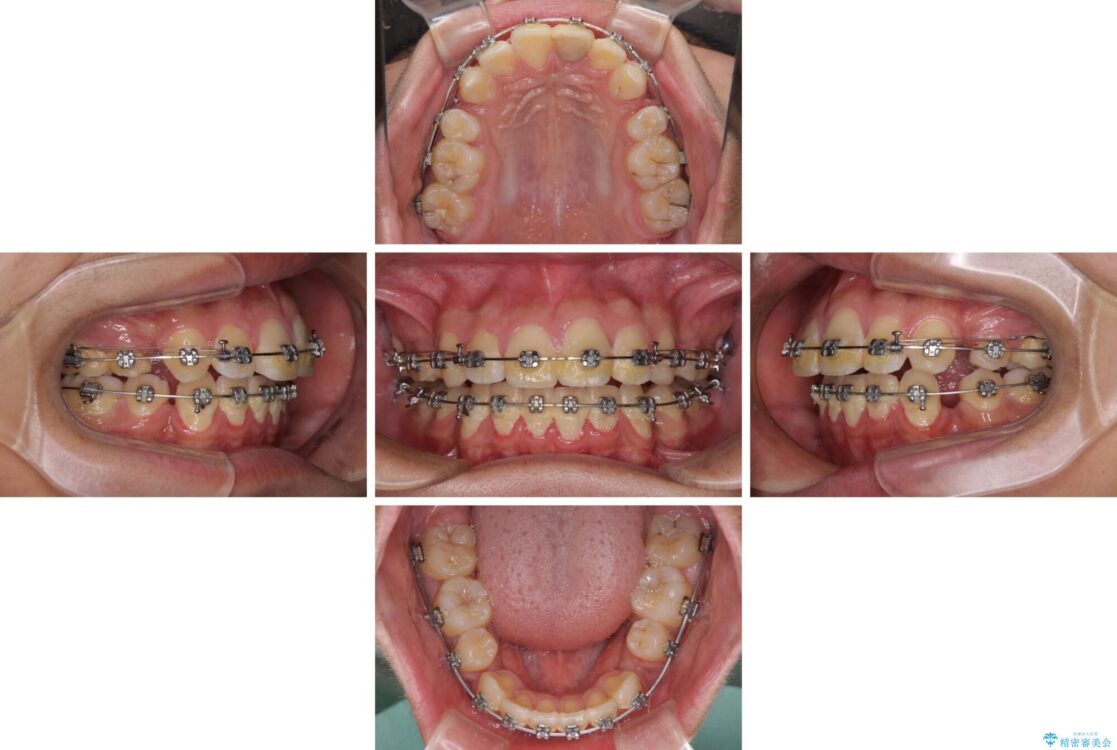

治療途中

• 膨らんだ口元 ワイヤー装置での抜歯矯正 治療途中画像

上下前歯が著しく前突している状態であったので、上下左右の第1小臼歯4本を抜歯し、ワイヤー装置にて矯正治療を行うこととしました。

小学生の頃に上顎前歯をぶつけ、歯の一部が破損している状態であったので、歯根が歯槽骨と癒着して移動しない可能性がありましたが、無事に治療を終えることができました。

受験勉強と重なり、舌のトレーニングが十分に行えず、高校生としてはやや長期間の治療となりました。